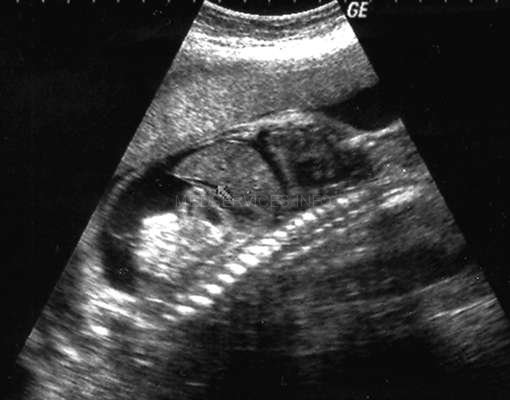

MEDISON.RU - Трехмерное УЗИ - атлас нормальной анатомии плода во II и III триместрах Пиелоэктазия почек плода. Гидронефроз почек плода.